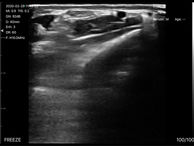

リニアプローブ

浅部組織の描出に優れ、血管・筋肉・神経などの観察に最適。

外来診療や救急現場、スポーツ医療など幅広いシーンで活躍します。